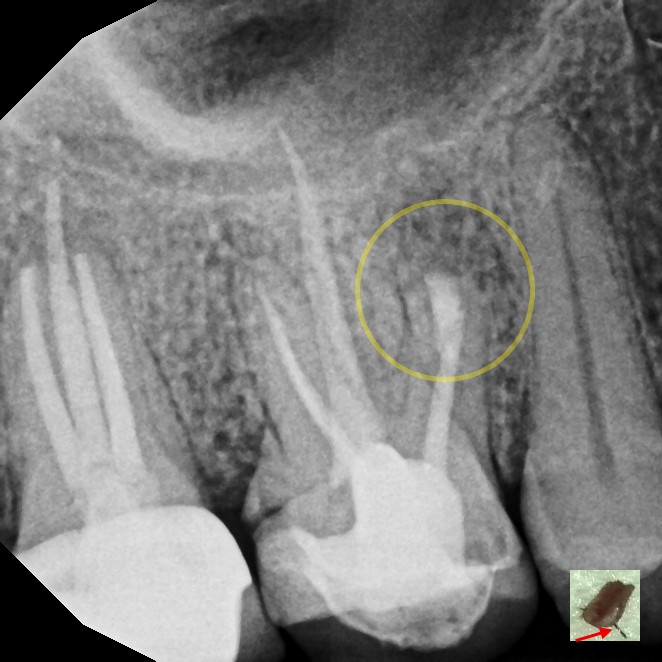

Endodontic surgery is a specialized dental procedure used to treat problems at the tip of a tooth's root or in the surrounding bone when standard root canal therapy isn't enough. The most common type, called an apicoectomy, involves making a small opening in the gum to access the root tip, removing infected tissue, and sealing the end of the root to prevent the infection from returning. This allows us to save the natural tooth and restore oral health, even in cases where other treatments have failed.

While it may sound complex, modern endodontic surgery is precise, minimally invasive, and performed under local anesthesia for your comfort. Most patients are surprised at how quick and straightforward the procedure is, and recovery is typically fast. Choosing endodontic surgery can help you avoid extraction, preserve your natural bite, and prevent the need for more extensive dental work in the future.